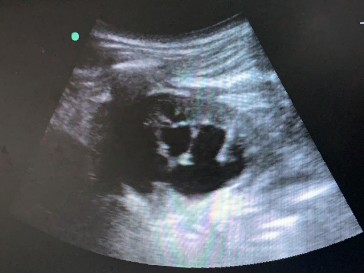

Hình 2.16. Siêu âm chọn vị trí vào đài thận

(Nguồn: chụp tại Bệnh Viện Trường Đại Học Y - Dược Huế)

Siêu âm chọn đường vào an toàn và hướng dẫn chọc vào đài thận (thường là đài dưới). (Hình 2.16).